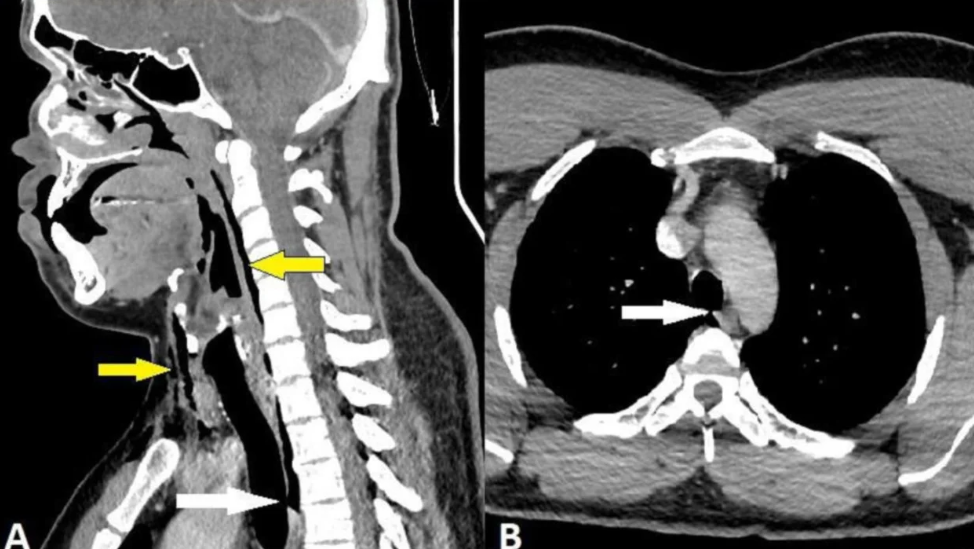

حيث أدت قوة العطس المكبوت إلى فتح ثقب صغير يبلغ حجمه 2 × 2 ملم في قصبته الهوائية. وقال الأطباء أن الإصابة السيئة حصلت بسبب قيام الرجل بإغلاق مجرى الهواء مما أدى إلى توليد ضغط عطس أقوى 20 مرة مما نختبره عادة.

وبعد إجراء الأشعة السينية، اكتشف أن الرجل يعاني من حالة تسمى انتفاخ الرئة الجراحي، حيث يمكن أن يعلق الهواء تحت أعمق الأنسجة في جسم الشخص. وقد انحصر الهواء في فقرات رقبة الرجل وكذلك في المسافة بين صدره ورئتيه. وفي نهاية المطاف، قرر الأطباء أن الرجل لا يحتاج إلى عملية جراحية وأن التمزق كان سببه "تراكم سريع للضغط في القصبة الهوائية أثناء العطس مع أنف مقروص وفم مغلق".